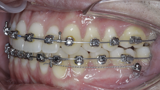

New Age orthodontics and orthopaedics with temporary anchorage devices